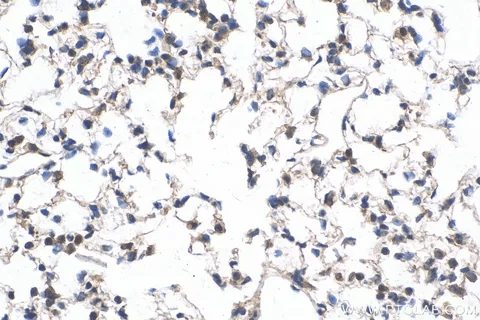

HEp-2 Cell Substrate Benefits

At the core of IFA is the HEp-2 cell substrate. HEp-2 cells are rich in nuclear and cytoplasmic antigens. This makes them perfect for spotting a variety of autoantibodies.

The human epithelial cell line (HEp-2) shows all kinds of cellular antigens. This boosts the test’s sensitivity.

Gold Standard Status in Autoimmune Testing

The IFA with HEp-2 cells is the gold standard for ANA testing. It can spot many autoantibodies with great specificity. This shows its reliability and wide use in clinics.